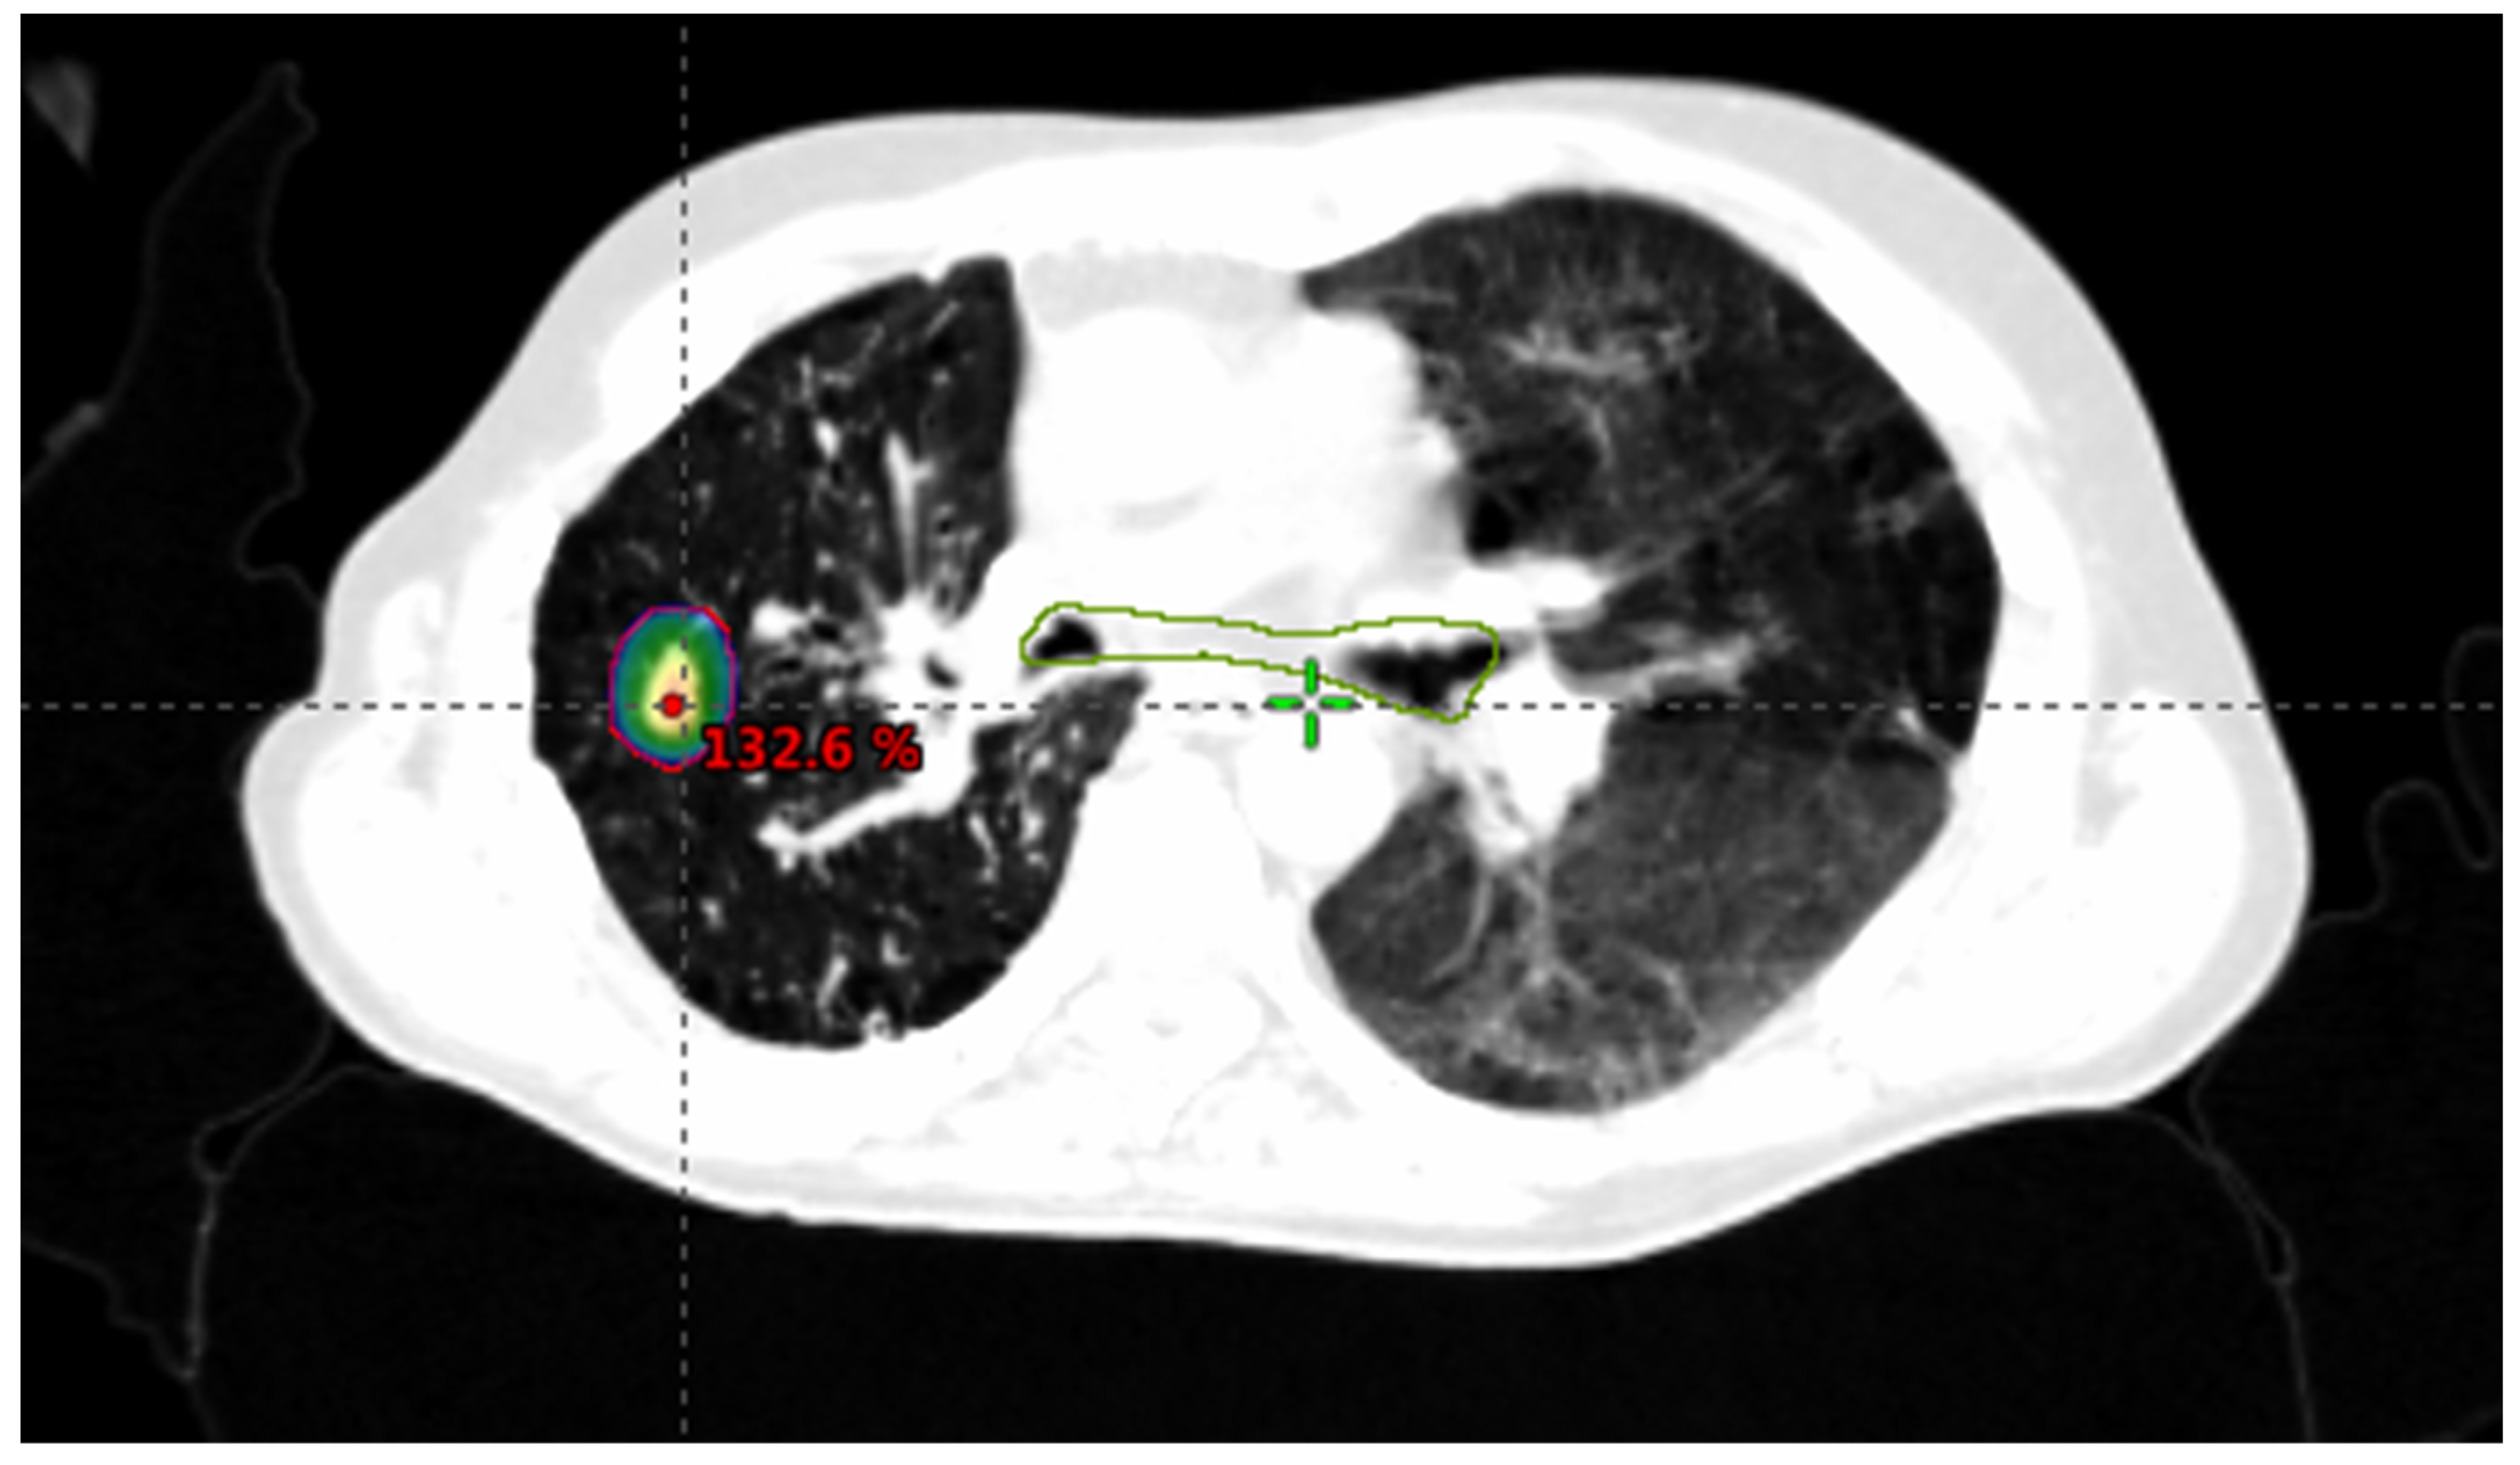

1.2. Stereotactic Body Radiotherapy (SBRT)

1.2.1. SBRT Technique

1.2.2. SBRT Dose

1.2.3. Criteria for Determining SBRT Suitability

1.2.4. SBRT Outcomes